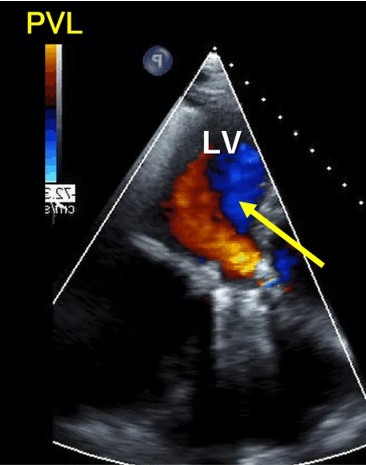

Blood tests showed an increase in totalbilirubin to 5.0 mg/dl, along with an increase in LDH and decreases in Hb andhaptoglobin, indicating hemolytic anemia. NTproBNP also increased to over 3000.The transthoracic echocardiogram showed the VSP at the membranous septum nearthe aortic PVL, and also moderate tricuspid regurgitation. Aortogram and CTscan demonstrated the severe aortic PVL with interventricular left to right shuntnearby.

Our heart team decided to perform both VSP and PVL closure by transcatheter technique because of the previous multiple open-heart surgery with high surgical risk score. Before percutaneous VSP closure, the oximetry-run exams revealed Qp/Qs 1.3 but the transesophageal echo(TEE) showed the EROA of aortic PVL was 0.51 mm2 and the defect size was 10.5 x 5.4 mm which meant severe PVL. We also confirmed the defect size of VSP with TEE, and the size was 8.1mm.

We performed this procedure under generalanesthesia with TEE. The first step was to close the VSP so that we manipulateda 5 Fr. Destination sheath with diagnostic JR4 catheter as mother and childtechnique. Inside of the system, 0,014-inch wire and microcatheter was advancedleft ventricle(LV) from aortic PVL. We turned the wire inside LV to access theVSP. We succeeded to have the wire advance to right ventricle(RV) through the LVand PVL. The next step was creating AV loop so that the 0.014 wire was snaredin the pulmonary artery and pulled out from right femoral vein. After creatingAV loop with 0.014 wire, the loop was exchanged to 0.035 wire and AMPLATZERDuct Occluder 6/4 was implanted into VSP. After closing VSP, we accessed insidethe PVL again and the wire was switched to super stiff one to advance theDestination sheath inside LV. Once the sheath was advanced in LV, 8mm AMPLATZERvascular plug 2 was deployed to close the PVL.